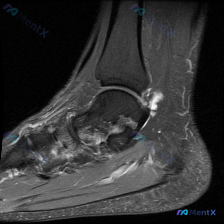

最近看到这份膝关节MRI读片请求,核心提示是软骨异常,整理了完整的资料和分析思路分享给大家: 基本影像信息 这份是膝关节矢状位MRI图像,属于T2加权/质子加权压脂序列,图像分辨率低、噪声大,仅能显示髌骨、股骨远端前部、胫骨近端前部和髌股关节局部区域,无法判断是内侧还是外侧层面。 影像具体发现 1....